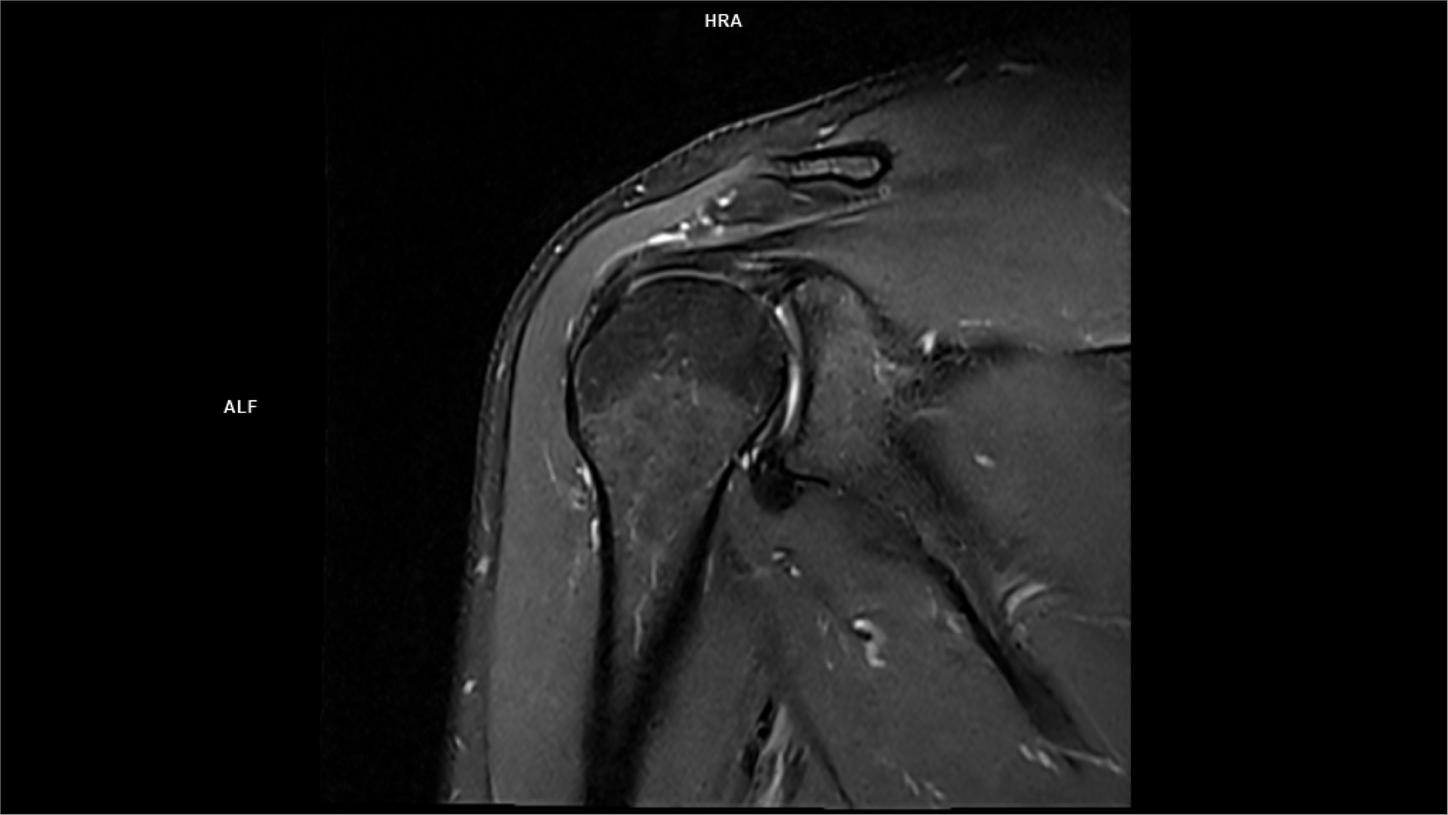

Normal shoulder MRI How to read a shoulder MRI Kenhub Coronal Pd Mri Protocol specifics will vary depending on mri hardware and software, radiologist and referrer preference, patient. The mri allows accurate assessment of any pathologic changes of the structures of the shoulder, including the glenoid labrum, the humeral head, the articular. The role of mri in. Many standard shoulder protocols will include the following fast spin echo sequences: In this article we. Coronal Pd Mri.

Coronal oblique proton density weighted resonance imaging of the left shoulder The BMJ Coronal Pd Mri The mri allows accurate assessment of any pathologic changes of the structures of the shoulder, including the glenoid labrum, the humeral head, the articular. Rotator cuff tears are the most common cause of shoulder pain and result in loss of strength and loss of stability of the shoulder. In this article we will discuss: Protocol specifics will vary depending on. Coronal Pd Mri.

Normal shoulder MRI How to read a shoulder MRI Kenhub Coronal Pd Mri Many standard shoulder protocols will include the following fast spin echo sequences: In this article we will discuss: The role of mri in. Protocol specifics will vary depending on mri hardware and software, radiologist and referrer preference, patient. Rotator cuff tears are the most common cause of shoulder pain and result in loss of strength and loss of stability of. Coronal Pd Mri.